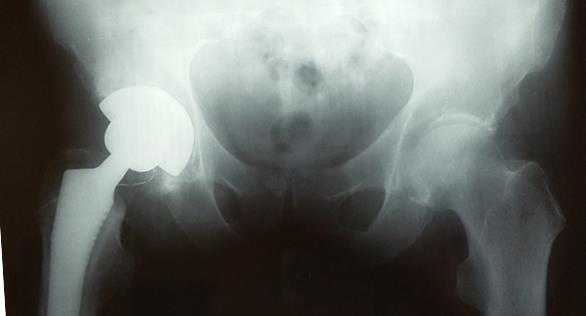

Пациентка Ж, 28 лет. Обратилась в К+31 в октябре 2017. Страдала врождённым подвывихом головки правого бедра, лечение в детсве не проводилось (на тот момент рутинного УЗИ скрининга в СССР не было, а к детскому ортопеду направляли не всех детей). В возрасте 23 лет отметила появление болей в области правого тазобедренного сустава. На протяжении последних 3 лет отмечала нарастание болевого синдрома, нарушение походки, ограничение амплитуды движений и постепенное укорочение конечности. Обратилась в К+31, выполнены рентгенограммы на которых визуализируется коксартроз 3 ст справа на фоне дисплазии правого тазобедренного сустава.

Принято решение о выполнении тотального эндопротезирование правого тазобедренного сустава протезом бесцементной фиксации пара трения керамика-керамика, с восстановлением длины конечности.

Снимки после операции. Длина конечности восстановлена. В сравнении со снимками до операции хорошо видно как восстановилось нормальное положение тазового кольца и поясничного отдела позвоночника. Пациентка была прооперирована в день поступления, переведена из РАО через 2 часа после операции, активизирована через 6 часов после операции. На вторые сутки обучена ходьбе с дополнительной опорой на костыли.